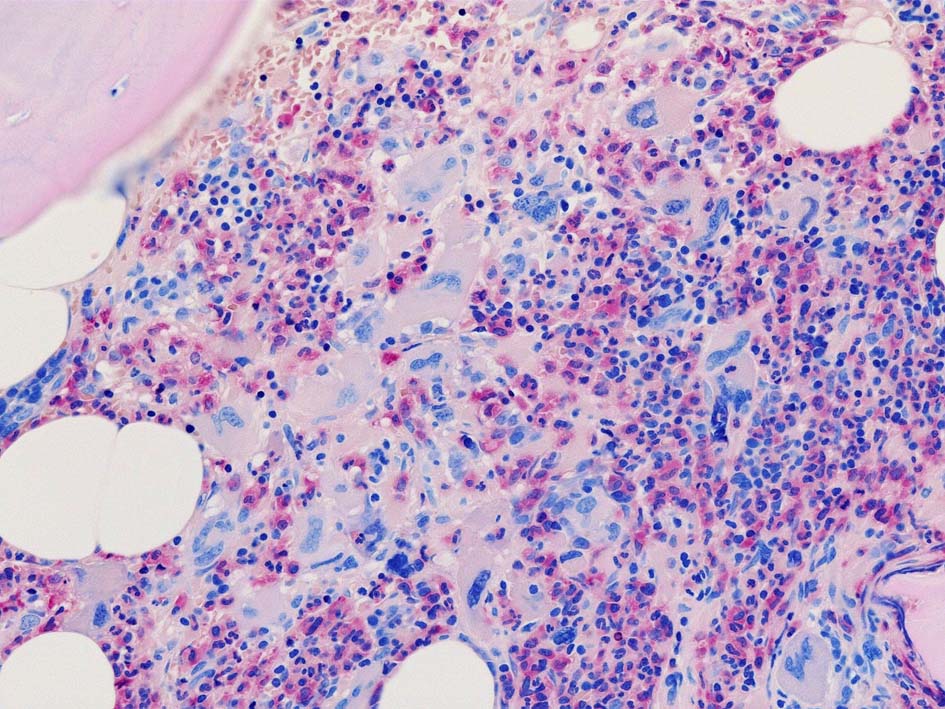

Case02; Meylofibrosis, overt fibrosis

77year-old female. 40歳時polycythemia veraと診断されていた.

[注] この症例は詳細は不明であるが, 過去にPVと診断されているため, PVに伴う二次性のmyelofibrosisの診断になる.

黒染する弾性線維の増生のほか, 赤く染まる膠原線維の増生が確認される. MF-2 fibrosis. 鍍銀染色の核染色をすると膠原線維の赤染がわからなくなるので行わない.